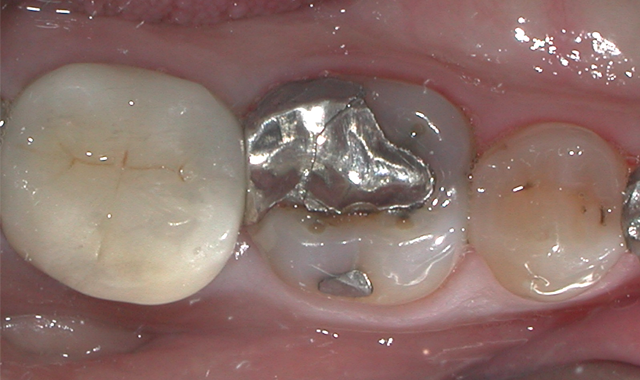

Fig. 1

A 60-year-old male patient presented complaining of pain from the lower right first molar. Upon clinical examination, tooth #30 was sensitive to percussion and had a fractured disto-occlusal-lingual amalgam.

After discussion with the patient and effective local anesthesia, the existing amalgam was removed to reveal caries extending into the pulpal tissue (Fig. 1).